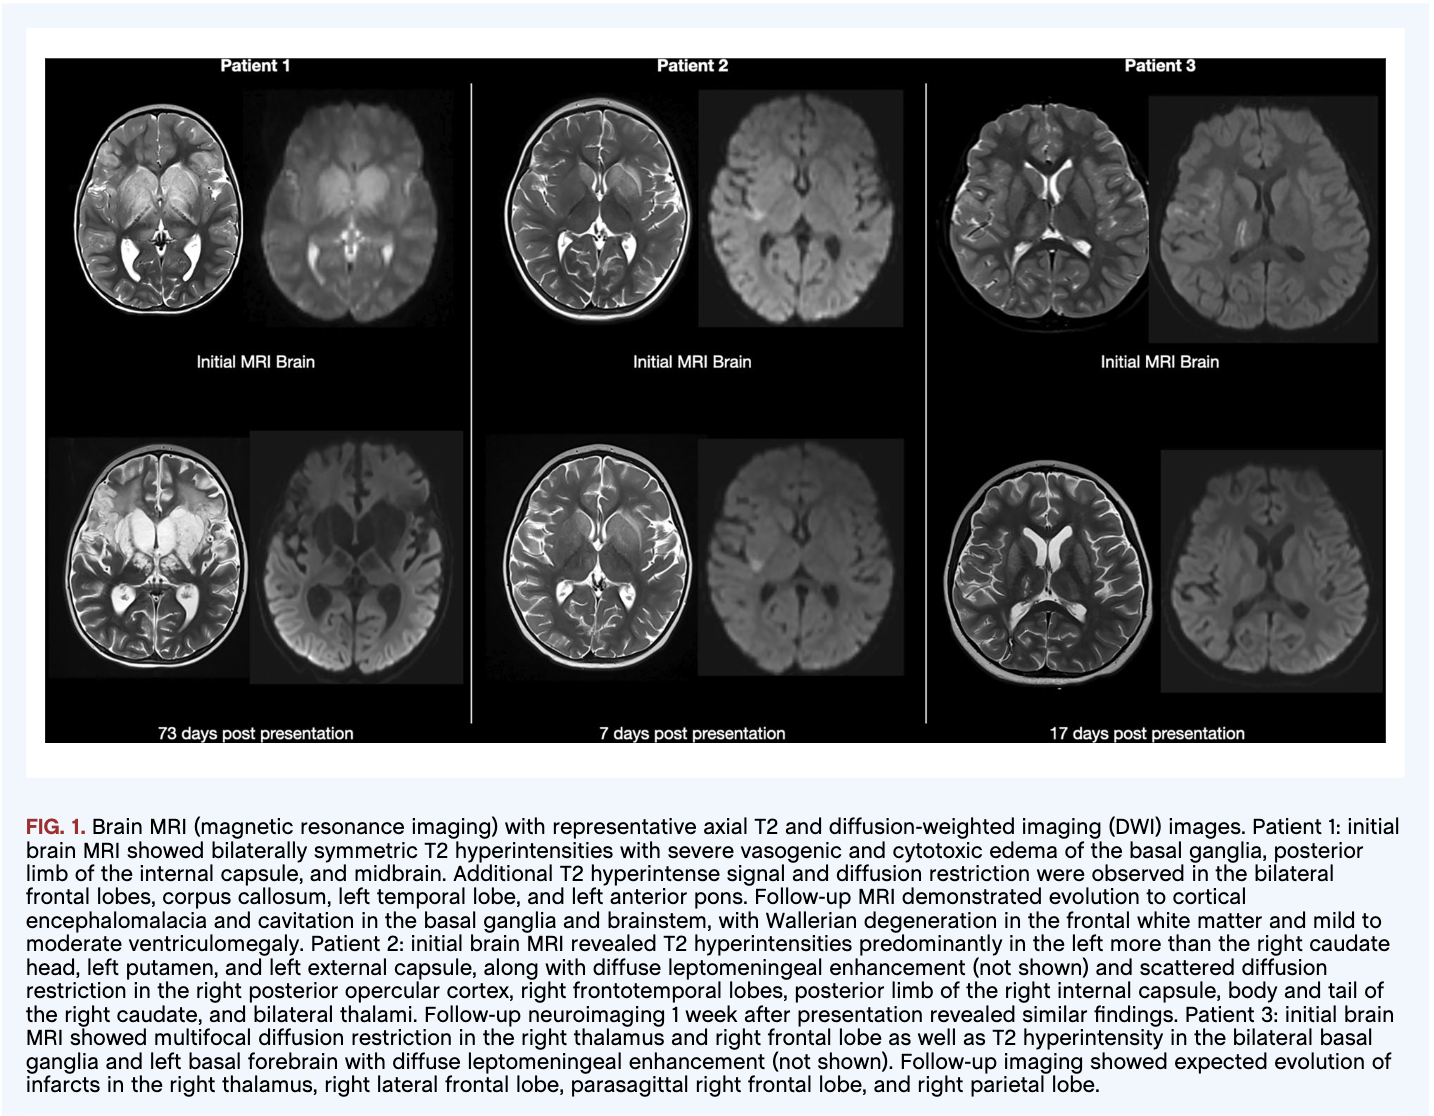

Results: We observed subcortical myoclonus and progressive generalized dystonia (Patient 1), transient dyskinesias and refractory focal dystonia (Patient 2), and generalized dystonia evolving into chorea and lingual dyskinesias (Patient 3). One patient displayed multifocal vasculitis on MRI angiography, a novel finding. All patients demonstrated bilateral T2 hyperintensities in the basal ganglia on MRI. In the acute period, all patients received high-dose corticosteroids, with two also receiving IVIG, interventions which have been posited to promote clinical improvement. Two patients required admission for management of worsening dystonia after their acute presentation. All patients required multiple treatments for dystonia and chorea throughout their disease courses, highlighting the refractory nature of their movement disorders.

Figure 1.